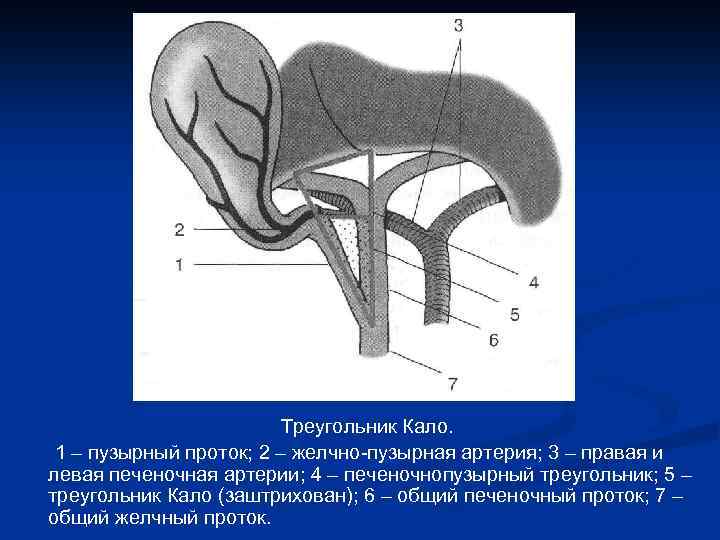

Треугольник Кало. 1 – пузырный проток; 2 – желчно-пузырная артерия; 3 – правая и левая печеночная артерии; 4 – печеночнопузырный треугольник; 5 – треугольник Кало (заштрихован); 6 – общий печеночный проток; 7 – общий желчный проток.

Треугольник Кало. 1 – пузырный проток; 2 – желчно-пузырная артерия; 3 – правая и левая печеночная артерии; 4 – печеночнопузырный треугольник; 5 – треугольник Кало (заштрихован); 6 – общий печеночный проток; 7 – общий желчный проток.